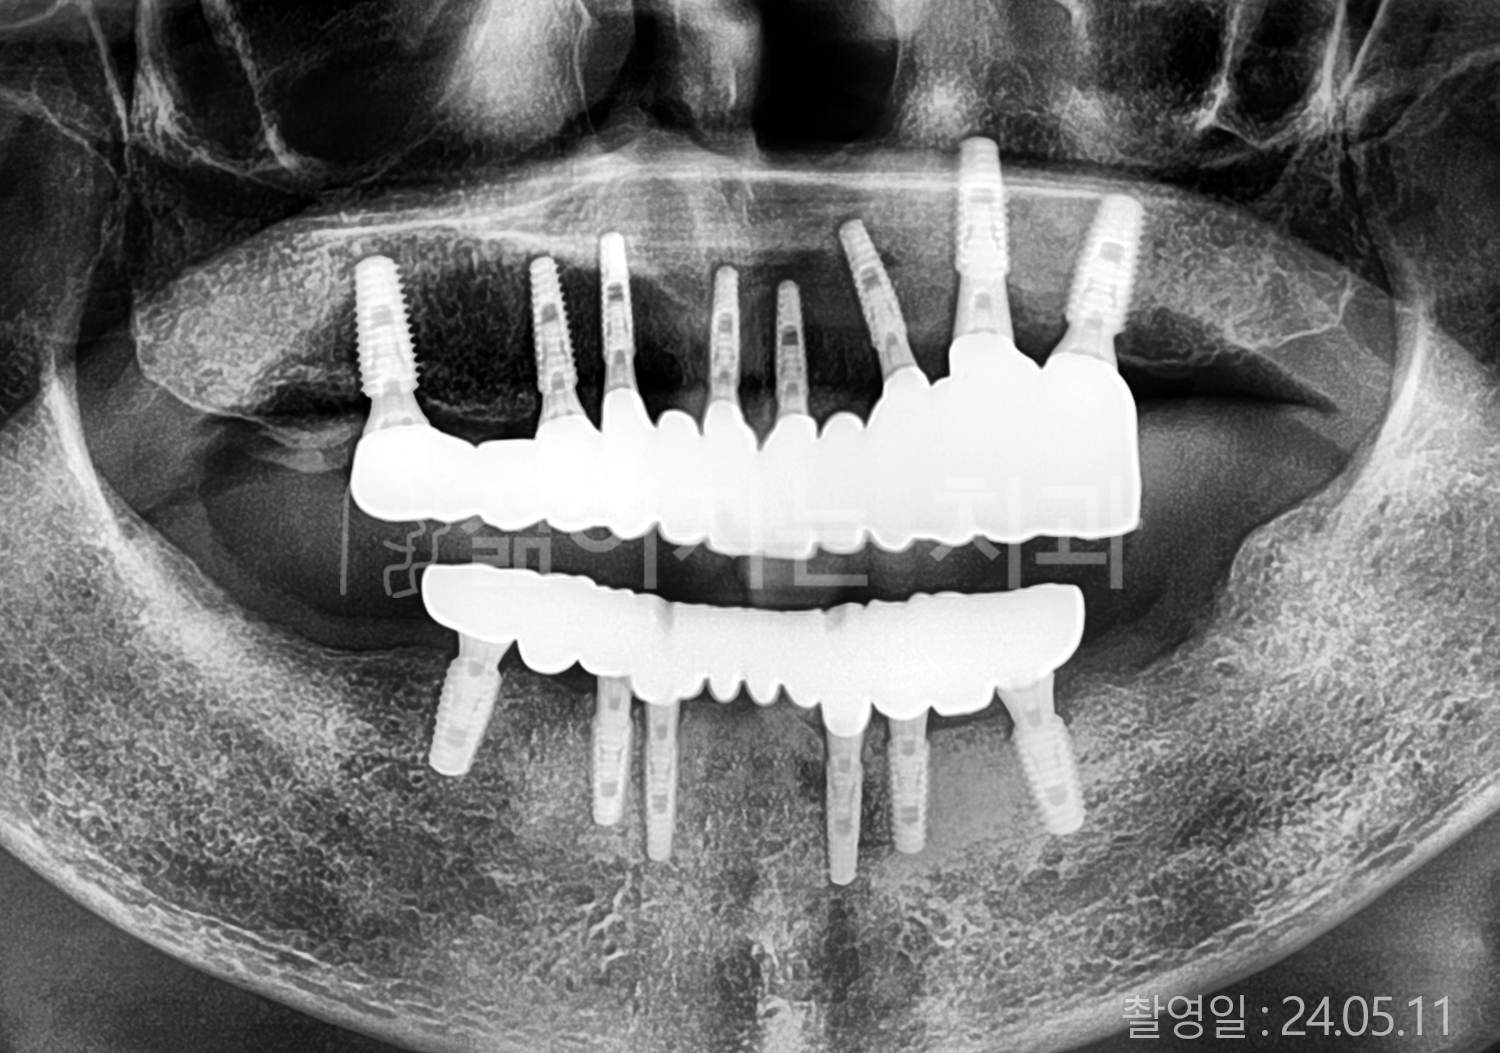

• 50대 전체치아 10개 이상 임플란트